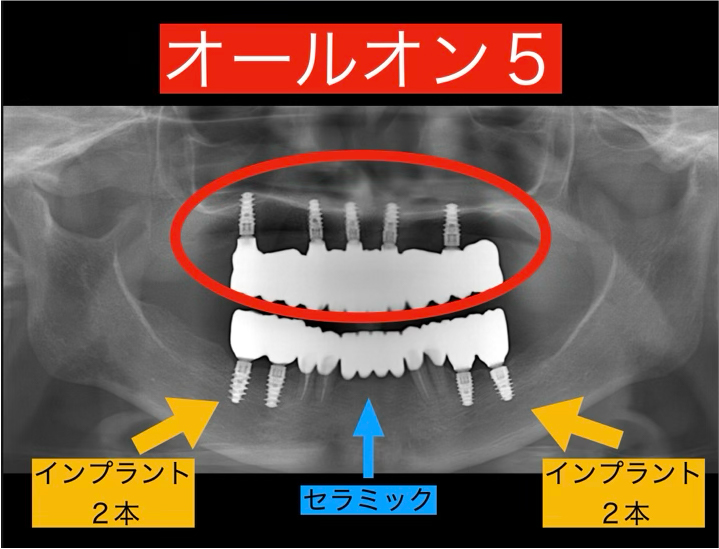

◆ 上顎:オールオン5(All-on-5)

上の歯は大部分が保存困難だったため、5本のインプラントで全ての歯を支える『オールオン5』という方法を採用しました。オールオン4は4本のインプラントで支える方法のこと言います。

これは、少ない本数のインプラントでしっかりと固定された美しい歯列を再現できる、見た目・機能性・耐久性を兼ね備えた最先端の治療法です。治療後は、まるで自分の歯のように噛めるようになります。

◆ 下顎:奥歯はインプラント、前歯はブリッジ

下の歯は、奥歯にインプラントを埋入し、前歯は残せる歯を活かしてブリッジで連結。

健康な歯をできる限り温存しながら、噛み合わせ全体のバランスを整える設計としました。